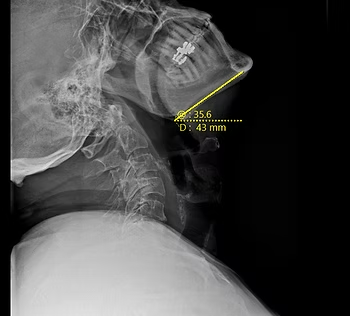

Motion X-Rays: Looking Up & Range of Motion

This is a view of a person's neck from the side and they're looking up. When this patient first started care, they could only look up at about 16 degrees. After completing an initial care plan, they are now able to look up at about 35 degrees, which is close to normal. At the end of the day, this person wasn't able to look up and the quality of life of that person was greatly diminished, in addition to the function of the body. The range of motion in the neck in this person was greatly increased. This can lead to fewer headaches, less tension, and more mobility in the cervical spine. A person who sees improvement in this area would have fewer blind spots while driving and better overall posture.

Cervical X-Ray After Initial Care Plan Completed: Patient standing normally, looking up as high as they are able